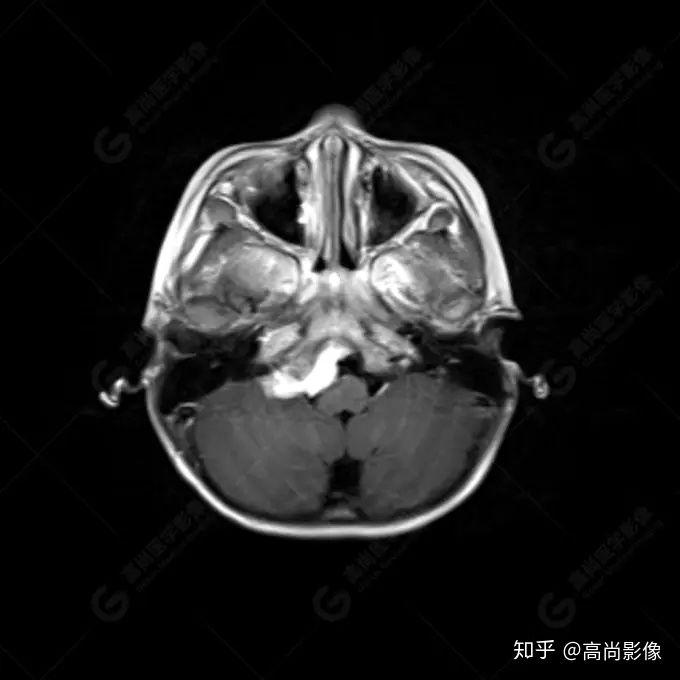

右側(cè)顳葉腫瘤切除術(shù)后(具體不詳):右側(cè)顳部骨質(zhì)不連續(xù)呈術(shù)后改變,右側(cè)顳葉術(shù)區(qū)見片狀長(zhǎng)T1長(zhǎng)T2信號(hào)影,F(xiàn)LAIR呈低信號(hào);術(shù)區(qū)后方右側(cè)顳枕葉見一巨大占位性病變影,邊界欠清,大小約6.2×5.8×4.3cm(前后×左右×上下),信號(hào)不均勻,T1WI呈等稍低信號(hào)間雜少許高信號(hào),T2WI呈高稍低混雜信號(hào),DWI示部分病灶彌散受限,相應(yīng)ADC圖減低,磁敏感序列見部分呈極低信號(hào),增強(qiáng)掃描可見明顯不均勻強(qiáng)化,鄰近硬腦膜及小腦幕增厚并明顯強(qiáng)化;另延髓右前方及右側(cè)橋小腦角區(qū)見一不規(guī)則形異常信號(hào)影,大小約3.2×1.3×3.7cm(左右×前后×上下),呈長(zhǎng)T1稍長(zhǎng)T2信號(hào),F(xiàn)LAIR呈等信號(hào),DWI未見受限,增強(qiáng)后明顯均勻強(qiáng)化,鄰近腦膜明顯強(qiáng)化。鄰近腦實(shí)質(zhì)及右側(cè)顳角明顯受壓;左側(cè)大腦半球未見局灶性信號(hào)異常,中線結(jié)構(gòu)稍左移。

右側(cè)顳葉腫瘤切除術(shù)后:現(xiàn)術(shù)區(qū)后方右側(cè)顳枕葉及延髓右前方占位,右側(cè)顳枕部硬腦膜及小腦幕明顯強(qiáng)化,結(jié)合既往影像資料,考慮為胚胎源性惡性腫瘤,如非典型畸胎樣/橫紋肌樣瘤(AT/RT)或原始神經(jīng)外胚層腫瘤(PNET)。